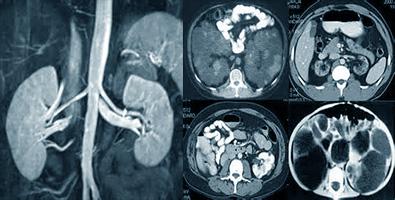

Магнитно-резонансная томография (МРТ) считается точным видом исследования почек и мочевыводящих путей. В её основе лежит исследование с воздействием на организм человека магнитных полей и электромагнитных волн. Кратковременные радиоволновые импульсы приводят ядра водорода в возбужденное состояние, аппарат фиксирует электромагнитный отклик частиц, выводя на монитор картинку, по которой можно определить точный размер внутренних органов а также, наличие патологий в них.

Магнитно-резонансная томография почек – это

современный неинвазивный диагностический метод, основанный на применении магнитного поля и радиочастотных импульсов, позволяющий исследовать почки в различных проекциях, благодаря чему получается более точное и информативное изображение. Проведение МРТ почек возможно как самостоятельный метод диагностики, так и в комплексе при осмотре брюшной полости.

Поскольку химический состав тканей организма неоднороден, картинка получается окрашенная в разные тона. При помощи МРТ удается достаточно четко диагностировать целый ряд заболеваний, таких как опухоли, отеки, вызванные инфекциями, опущения почек после удара, деформации внутренних органов, а также кисты на них.